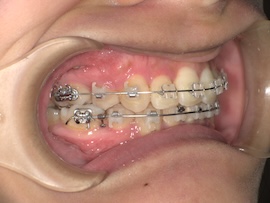

前回から1ヶ月後の歯並びはこんな感じです。

左上親知らずの牽引を始めてたった1ヶ月ですが、かなり出てきている気がします。